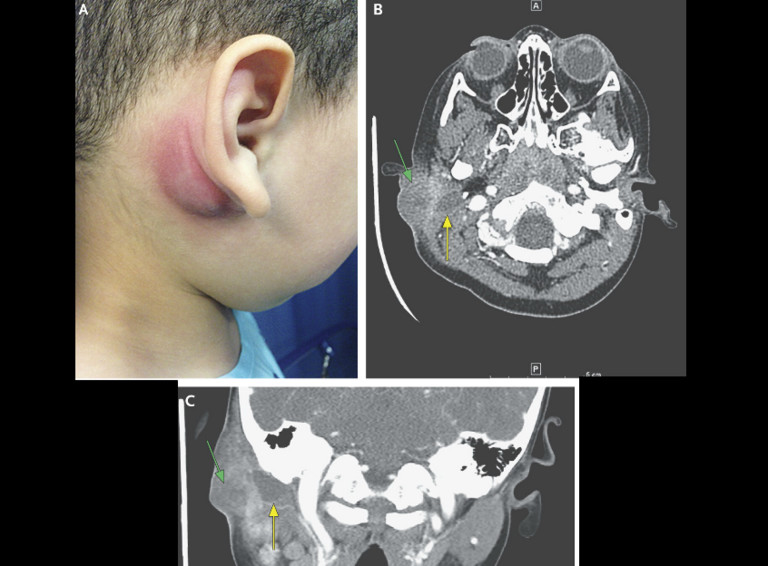

При осмотре: заушная область отечна, флюктуирует и болезненна (рисунок А), белый секрет выделяется в наружный слуховой проход. При компьютерной томографии височной кости (рисунок B и C) выявлена область низкоинтенсивного наполнения( желтая стрелка) и признаки воспаления в перисосцевидной области (зеленая стрелка). Признаков инфекционного процесса в среднем ухе или сосцевидном отростке нет. Пациент был взят в операционную, где при осмотре правого наружного слухового прохода обнаружен небольшой свищевой ход, который указывает на наличие первичной кисты жаберной щели.При слабом нажатии на отекшую заушную область, гной выделялся через свищевой ход и костнохрящевое соединение в ушной канал.